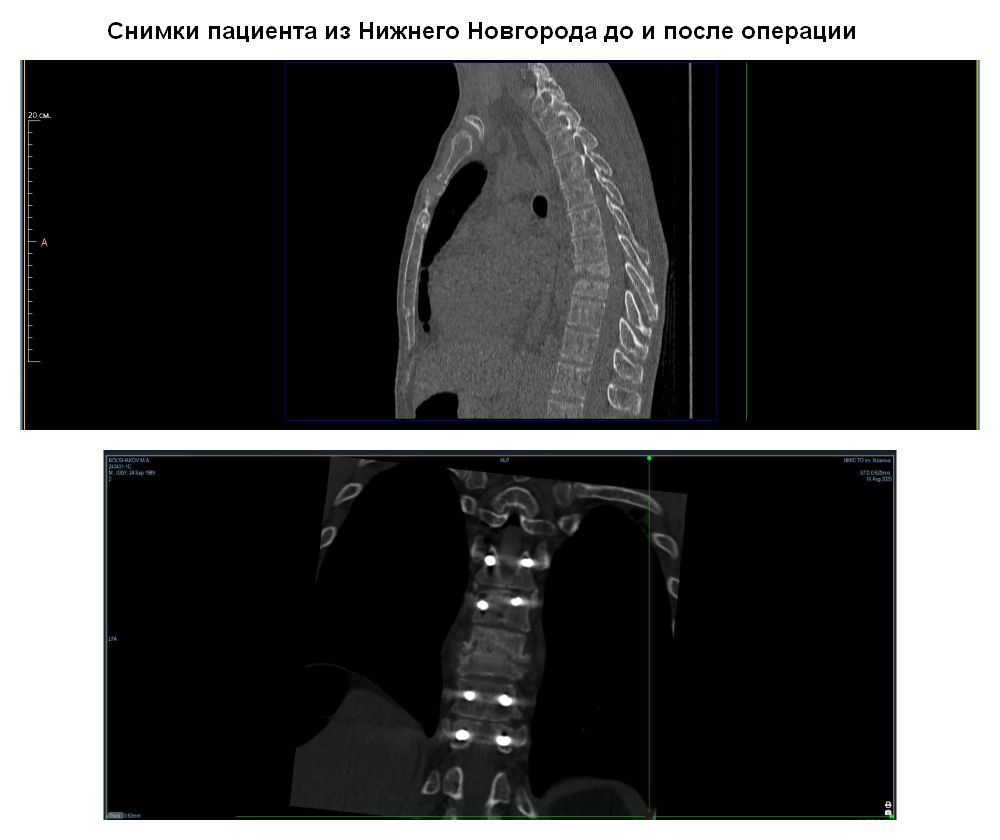

Один из последних ярких примеров – случай с 36-летним пациентом из Нижнего Новгорода. Два месяца молодой человек находился в лежачем состоянии в стационаре неврологии по месту жительства, лечением костно-суставной инфекции там не занимаются, поэтому был собран консилиум специалистов спинального профиля при участии экспертов группы гнойной вертебрологии Центра Илизарова. Было принято решение о переводе пациента в Курган.

- Мы оперативно среагировали, поняли, что можем помочь этому пациенту, а далее Минздрав Нижегородской области оформил транспортировку пациента службой медицины катастроф и его доставили к нам. В Клинике костно-суставной инфекции ему выполнили весь спектр диагностики, включая малоинвазивную биопсию для выбора тактики лечения. Получив общие результаты исследований, мы провели ревизионную операцию с санацией и установкой транспедикулярной конструкции, это позволило пациенту начать раннюю реабилитацию. И у нас молодой человек начал ходить. Госпитализацию мы решили разбить на несколько этапов: вначале проведем реабилитацию со специалистами нашей клиники, электростимуляцию для купирования неврологического дефицита, а далее выполним второй этап хирургического лечения, имплантация из бокового плеврального доступа.